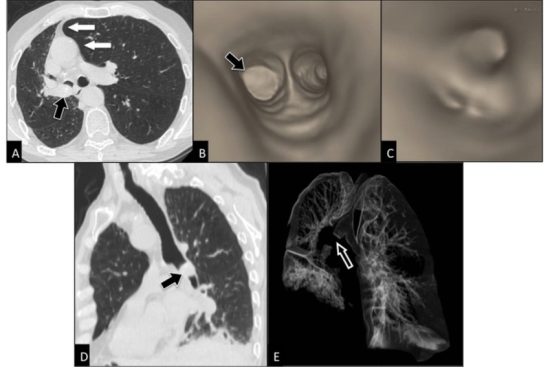

CT (Computed Tomography) scans are advanced imaging tests that take multiple X-ray measurements from different angles and process them with computer algorithms to produce detailed cross-sectional images of your internal organs, bones, and tissues.

- Chest CT Scan: Used to detect lung cancer, infections, or lymph node enlargement.